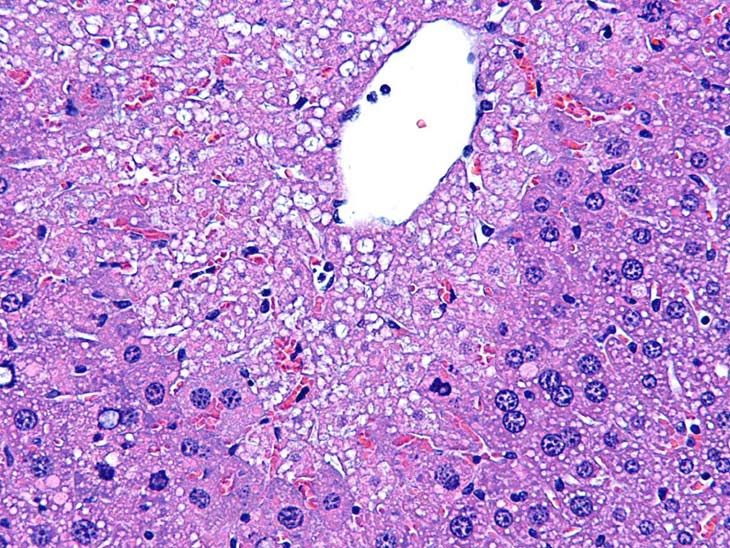

Multiple granulomas are present in this Tg.AC mouse treated with rotenone.